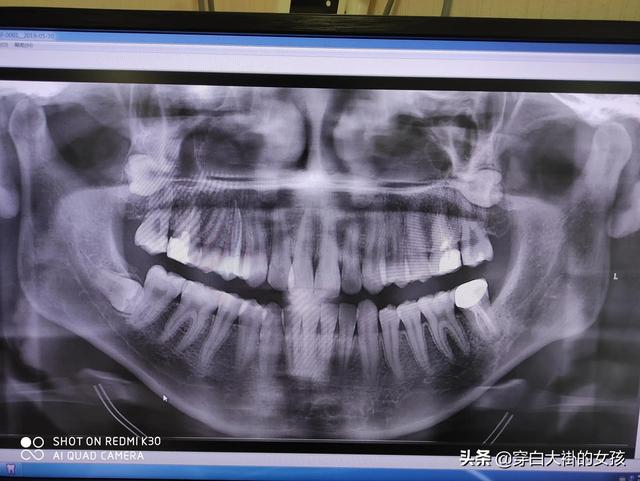

Die Zähne sind ein wichtiges Organ des menschlichen Körpers, und die Hauptfunktion der Zähne ist neben dem Kauen der Nahrung die Erhaltung der Gesichtsästhetik, die Koordination und die Unterstützung der Aussprache.

Funktionen der Zähne - Kauen

- Zerreißen Sie die Nahrung, um sie leichter schlucken zu können;

- Der Kauvorgang stimuliert die Nerven um die Zahnwurzeln herum, was wiederum das Gehirn dazu anregt, reflexartig die Peristaltik zu regulieren. Gleichzeitig wird die Sekretion von Verdauungssäften aus der Gallenblase und der Bauchspeicheldrüse angeregt, was die Verdauung weiter fördert.

Funktionen der Zähne - zur Unterstützung der Artikulation

- Der Schall wird von den Stimmbändern erzeugt und von mehreren Organen, einschließlich des Mundes und der Nasengänge, koordiniert, um eine Sprache zu bilden, die wir verstehen können.

- Wenn Sie keine Zähne haben, wird Ihre Sprache undeutlich sein. Wenn Ihnen Zähne fehlen, wird Ihre Sprache undicht.

Funktionen der Zähne - Erhaltung der Ästhetik und Harmonie des Gesichts

60%-70% der visuellen Wahrnehmung des menschlichen Gesichts kommt aus dem unteren 1/3 des Gesichts, wenn die Zähne nicht gerade sind, der Mund vorsteht, Baotian, usw., sieht das untere 1/3 des Gesichts nicht gut aus. Es gibt ein Sprichwort, das besagt: "Die obere Gesichtshälfte bestimmt die Schönheit, die untere Gesichtshälfte bestimmt die Hässlichkeit". Egal wie gut die Konturen der fünf Gesichtszüge sind, solange es ein ernsthaftes Problem mit dem vorstehenden Mund gibt, wird es sehr schwierig sein, ihr Temperament hervorzuheben. Wenn Sie denken, dass Sie nicht gut genug aussehen, und Sie haben auch fehlende Zähne oder ungleiche Zähne, wird es Ihr Gesicht Wert noch mehr zu senken.